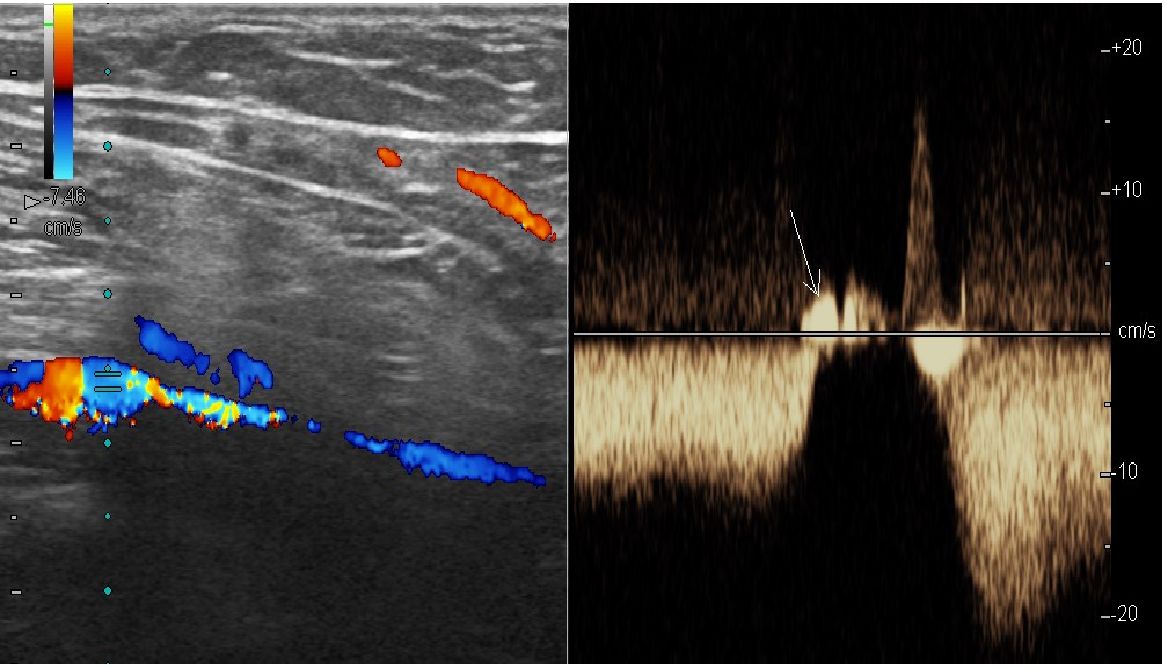

On the basis of USDS data, by the 14th day after surgery hemodynamic signs of dysfunction of the deep shin veins persisted in 4 patients of II group. Manual tests with proximal and distal compression revealed bidirectional «pendulum-like» signal in deep shin veins (flashes of yellow light filling the lumen of vessel) that permitted to diagnose segmental varicose transformation with reflux through perforating veins (Fig. 1).

Fig. 1. Sonogram of deep shin vein, USDS. Performed with distal compression test. Retrograde blood flow is recorded